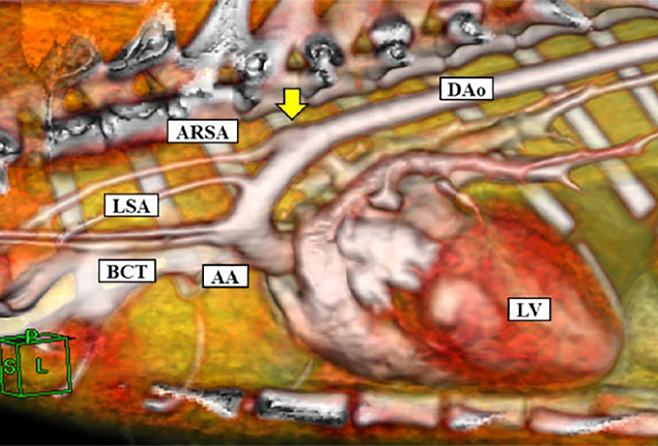

• 臨床検査に関する補助技術 (特に、腹部および心臓の超音波検査、内視鏡検査、内分泌検査など)